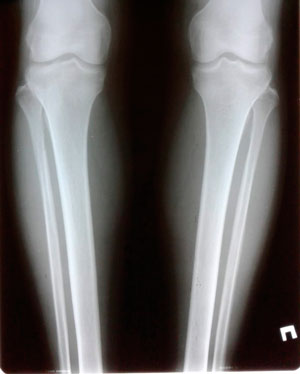

Исходник - 42 года.

Дата операции - 27.05.2020